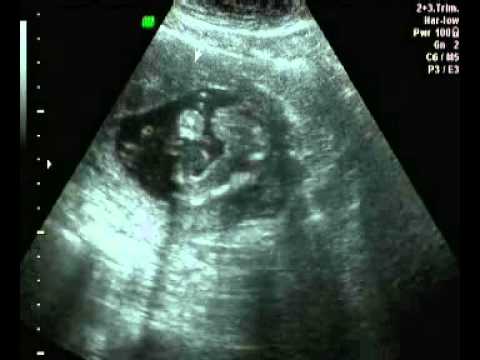

2D Scanning video

uge 24+2

MinGraviditet Redaktion

-

april 29, 2016

0

Får målt hovedet, maven og lårbensknoglen